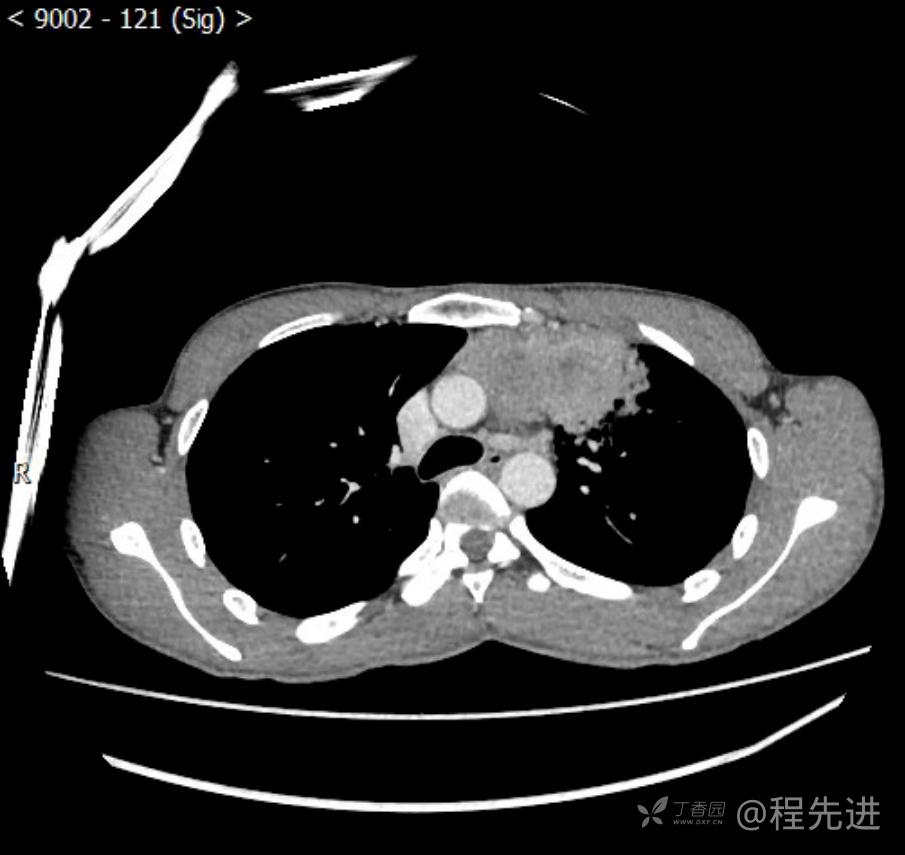

主诉:反复咳嗽1月,发现“纵隔”占位半月,乏力10余天。

现病史:患者1月前无明显诱因出现咳嗽,以夜间为著,伴有少量白痰,无发热,无胸痛、咯血,无痰中带血,未予重视,半月前外院行胸部CT检查发现“左前上纵隔”占位,未予进一步检查及治疗。近10余天自觉乏力,逐渐加重。